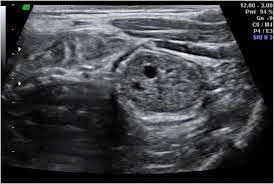

2)Διάβαση παχέος εντέρου. Με τη χρησιμοποίηση ενός υγρού που λέγεται βάριο και κάνει το παχύ έντερο να φαίνεται άσπρο σε ακτινογραφίες. Έτσι παίρνονται πολλές φωτογραφίες. Ο πολύποδας φαίνεται μαύρος, έτσι είναι σχετικά εύκολο να τον δει κανείς.

3)Σιγμοειδοσκόπηση ή κολονοσκόπηση: Αυτή τη μέθοδος θεωρείται η καλύτερη γιατί μπορεί ο γιατρός να δει εσωτερικά το έντερο, τμήμα του ή όλο το παχύ έντερο άμεσα σε οθόνη, υπάρχει δυνατότητα λήψης βιοψιών ή ακόμη αφαίρεση του ίδιου του πολύποδα κάτω από ορισμένες προϋποθέσεις (συνήθως σε κλινική).